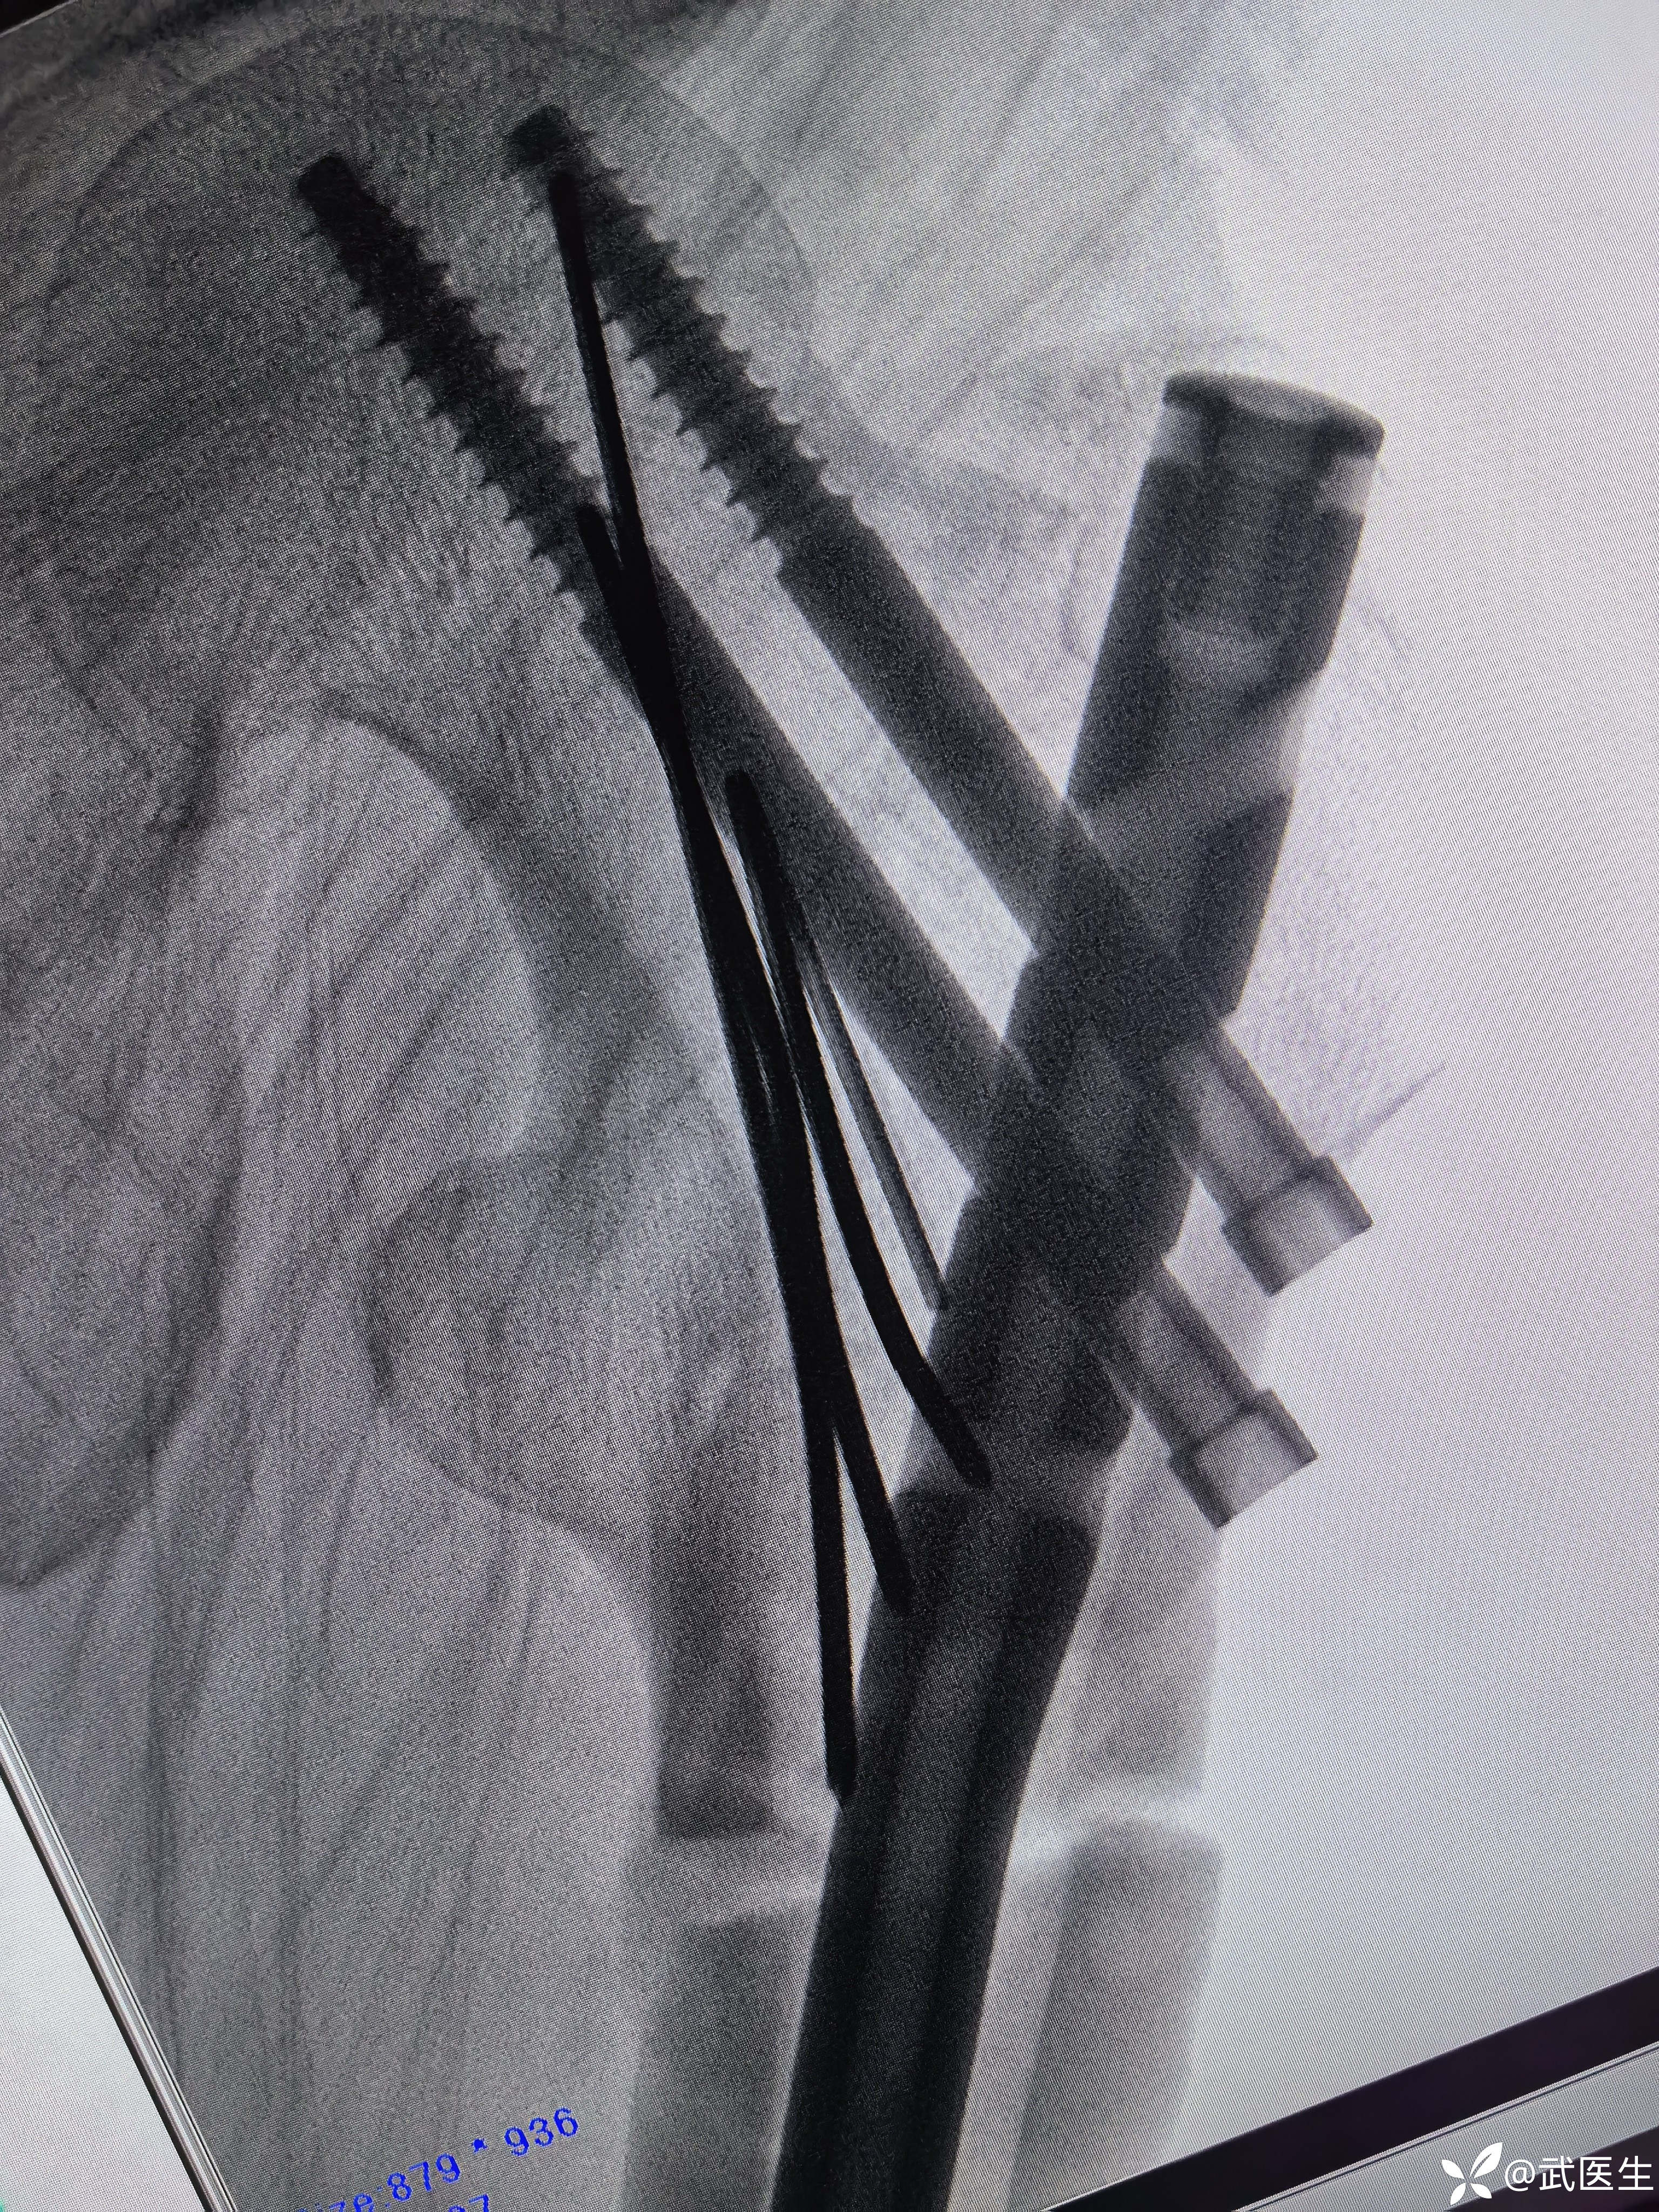

髓内钉已经很深了,头钉有点偏上,不再更换短钉了

阻挡克氏针更换为阻挡钉

最终

头钉有点偏上,髓内钉也算顶天立地。